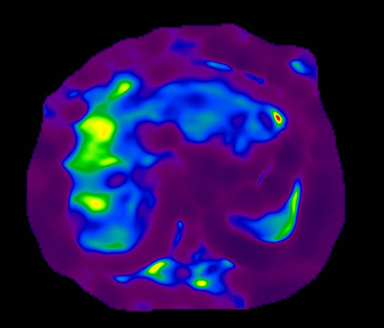

Figure 5. Color Elastogram, no mask, scale 0-8K

Figure 6. Color Elastogram, with mask, scale 0-8K